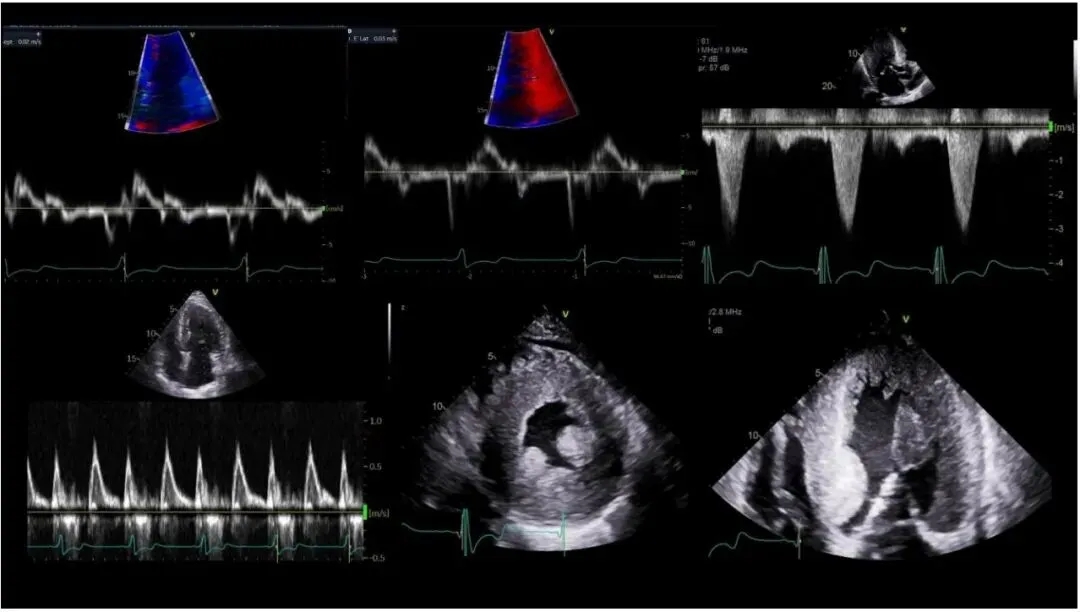

图2 法布雷病超声心动图表现的代表性病例

上左、下左和上中:左心室舒张功能障碍;上右:左心室流出道梗阻(LVOTO);下右和下中:左心室肥厚(LVH)。